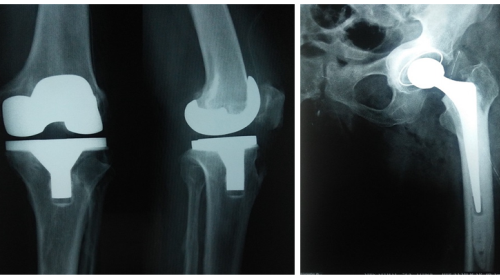

Other than the treatment for fractures he introduced spinal injury management in our region. He has done many knee joint and hip joint replacements. Because of that many old age arthritic patients are walking around without pain.

Joint replacement surgeries

Human knee joints are strong. They help in standing, walking, sitting, squatting, crosslegged sitting, jumping and swimming. They are very useful for all kinds of human body moments. But when they bear a lot of weight and work too much of time they start degenerating. Initially, the soft tissues in between the bones of a joint Which are known as meniscus start degenerating.